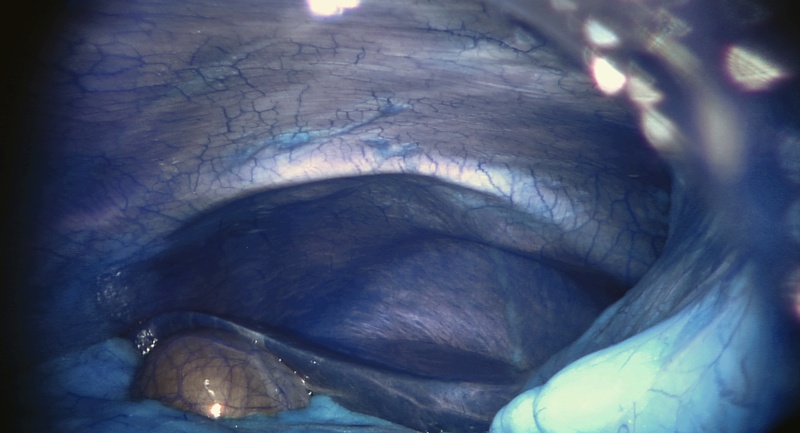

達文西機械手臂 Da Vinci

片長:25分

2013里斯本獨立影展最佳短片獎。這是來自機器的視角,從機械構造延伸的人類雙眼,透過儀器螢幕,將手術過程轉化為自身的視覺語言。